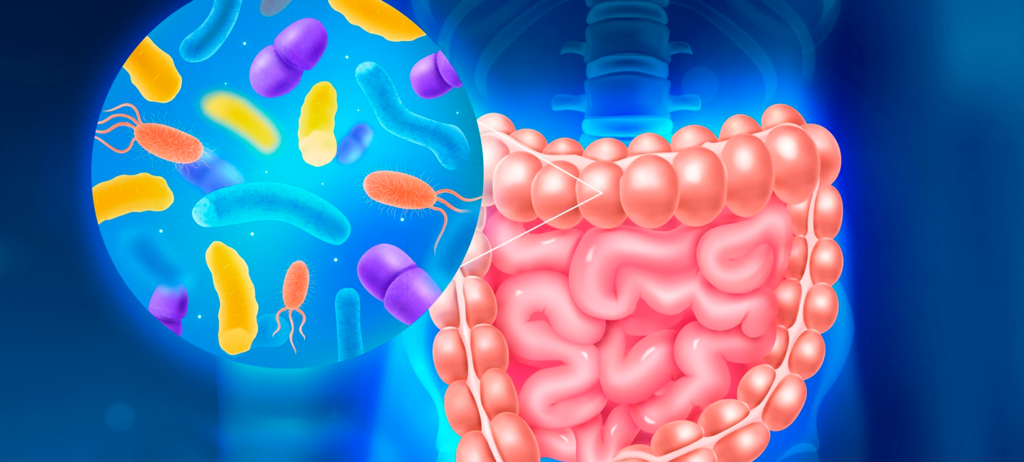

Curso Online Electrocardiografía Básica

Desarrollar habilidades para la correcta toma, análisis e interpretación de un trazado electrocardiográfico básico.